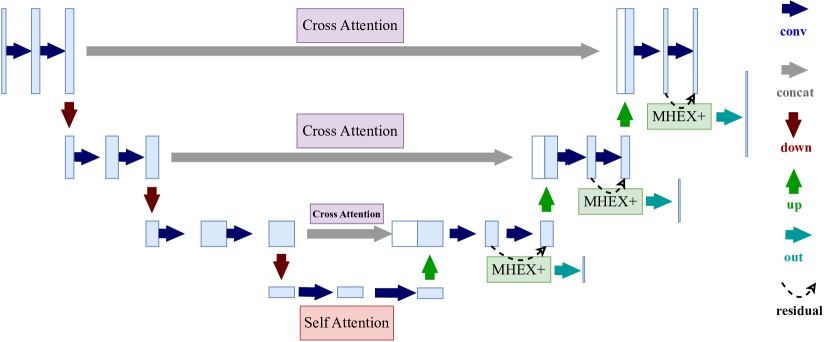

U-Net-like networks consist of three stages: downsampling (encoder), extracting low-level features; bottleneck, capturing global context; and upsampling (decoder), reconstructing the segmentation map.

We construct residual connections in the double convolution module across all decoders in U-Nets to integrate MHEX+, following the structural design principles of ResNet [26]. For U-Net++, we use the densely connected version rather than the deep supervision version, as MHEX+ already incorporates deep supervision. Please refer to Figure 2.